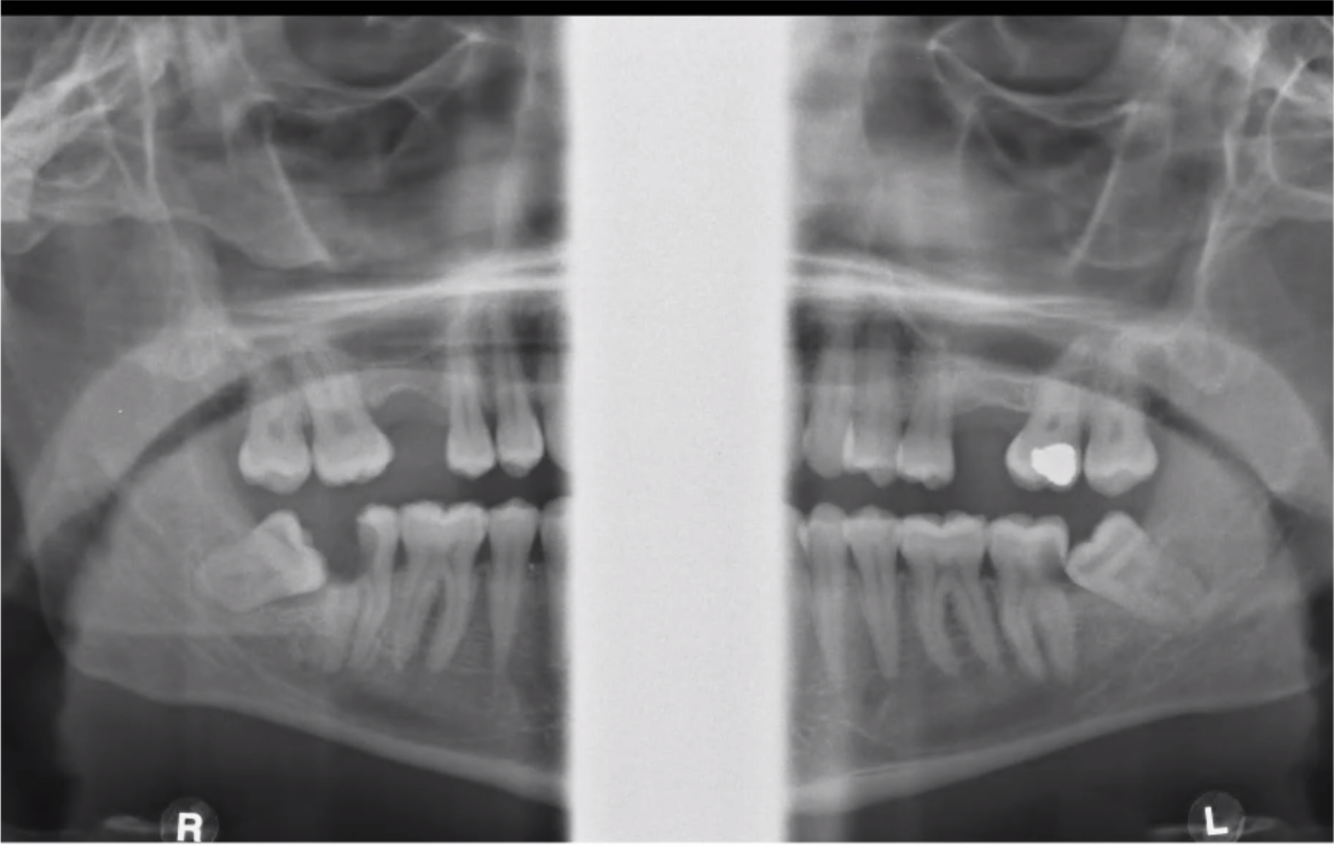

What do you see in this image?

Caries in both lower second molars

What type of impaction are these third molar?

Vertical

Right - Vertical

Left - Mesio angular